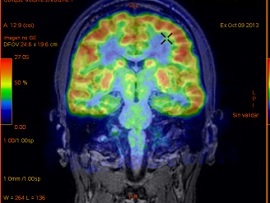

پرتوهای گاما شبیه پرتوهای ایکس بوده و توسط دستگاهی به نام دوربین گاما شناسایی و سپس تبدیل به سیگنال الکتریکی شده و به کامپیوتر ارسال می شود. کامپیوتر با تبدیل شدت های مختلف ماده رادیواکتیو ساطع شده از بدن بیمار به رنگهای سایه های مختلف خاکستری ، تصویر گاما اسکن را ایجاد می کند.

تصاویر گاما اسکن به چه صورتی نمایش داده می شود؟

تصاویر گاما اسکن بر روی کاغذ قابل چاپ است و یا بصورت سی دی ارائه می شود که هر کدام مشکلات خاص خود را دارند نظیر پاره شدن کاغذ یا عدم کیفیت کافی تصاویر چاپ شده و یا لود نشدن سی دی در کامپیوتر. ازین رو با پیشرفت فناوری امروزه از روشهای جدیدتری بصورت ارائه بارکد دوبعدی یا کیو آر کد تصاویر بیمار استفاده می شود که به راحتی می توان در موبایل تصاویر گاما اسکن بیمار را مشاهده نمود.